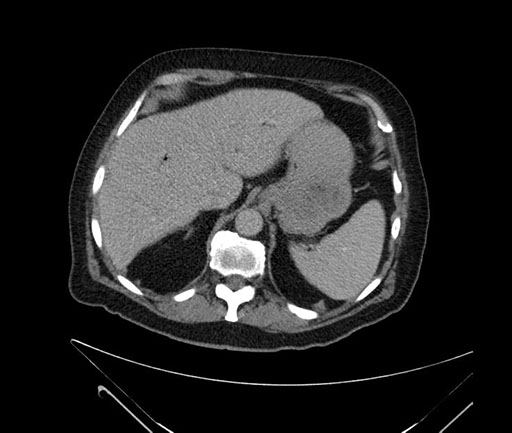

Whipple (pancreaticoduodenectomy) [case 7]

Axial - 3 months prior